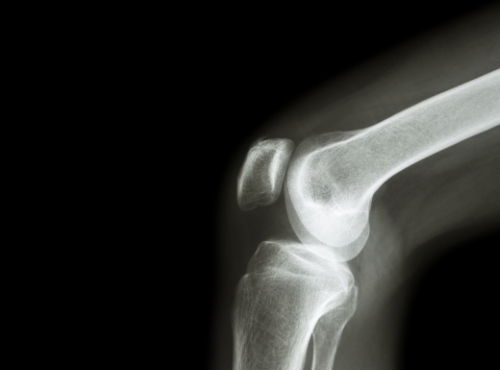

When the patella, or kneecap, does not remain in place as the leg straightens or bends, it is called patellofemoral tracking syndrome. Many people believe that the kneecap only moves up and down, but that is not accurate. Actually, the kneecap is very mobile, rotating and tilting so that there are a variety of contact points between the femur and patella. The most common way that this disorder presents is the kneecap extends too far to the outside of the leg. Less common is when the kneecap shifts to the inside. The result is pain (sometimes severe) and limited mobility.

Understanding the syndrome means understanding the mechanics of the knee joint. The thighbone (femur) and lower leg (tibia and fibula) are joined by the knee, a large, complex hinge. A groove runs along the front of the joint, where the thighbone ends. The patella sits in the groove and is held in place by a network on the sides by ligaments and at the top and bottom by tendons. The underside of the kneecap is a layer of cartilage that allows it to move easily, or glide, along the groove. When there is a problem with any of the parts that make up the knee it can lead to patellofemoral tracking syndrome.